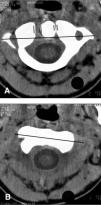

Figura 1 A y B.TC entre agujero occipital y C3. Se observa subluxación rotatoria C1-C2 con descentramiento de la apófisis odontoides.

Niño de 14 años que fue remitido a nuestro centro por cuadro de dolor cervical en región mastoidea derecha y fiebre de 7 días de evolución que no había mejorado tras tratamiento antibiótico y antiinflamatorio oral. Con el diagnóstico de mastoiditis aguda se ingresó con antibioterapia parenteral. Se practicó radiología simple, TC de mastoides así como gammagrafía ósea sin hallazgos significativos. La fiebre desapareció a las 24 h del ingreso pero persistía el dolor cervical por lo que se realizó una TC cervical que mostró una subluxación rotatoria atlanto-axial (fig. 1). Posteriormente el niño recordó que se había lanzado desde 4 m de altura sobre una cama elástica golpeándose la región cervical. La evolución posterior con tratamiento conservador fue satisfactoria.